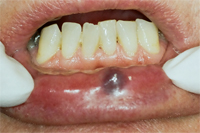

Die Abb. 1 bis 4 sollen als anschauliche Beispiele für gesunde und kranke Fundamente dienen.

Ein 31 Jahre alter Patient zeigt einen starke Zahnfleisch-Rückgang im Oberkiefer (Abb. 1 und 3) und wir beschliessen, diese Rezessionen zu behandeln.

Der Erfolg der Behandlung ist deutlich in den Abb. 2 und 4 zu sehen. Sehr augenfällig konnte die Situation um den Eckzahn im linken Oberkiefer verbessert werden (vergleiche dazu Abb. 3 vorher und Abb. 4 nachher).